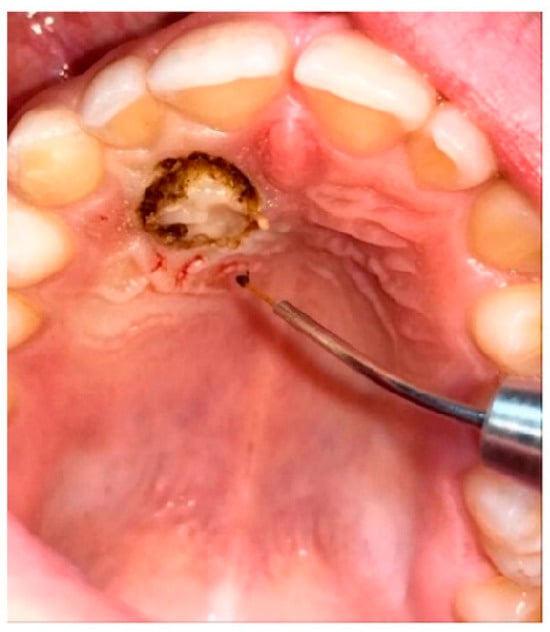

The major axis of the canine and the interincisor midline were traced on the panoramic X-ray. The angle between these two lines constitutes the inclusion angle α. The angulation of the canine with respect to the midline is generally considered to be mild if between 0° and 15°, moderate if between 16° and 30°, and severe if greater than 30° (Figure 1).

Figure 1.

Angle α of inclusion measured on OPT. The α angle of element 1.3 measures 48°; the α angle of element 2.3 measures 42°.